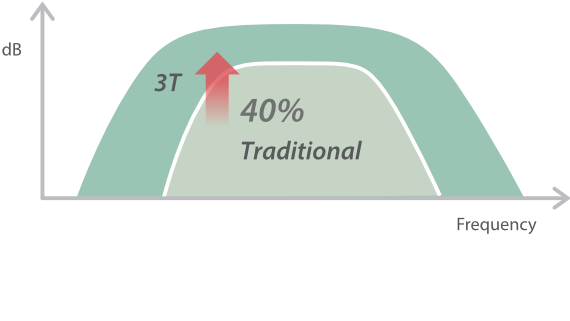

?????? ??? ???? ?? ???? ??? ??? ??? ???? ??? ??? ??? ?? ??? ???? ?????. ??? ?? ????? ???? ???? ??? ?? ??? ???? ?? ???? ??? ???? ???? ????.